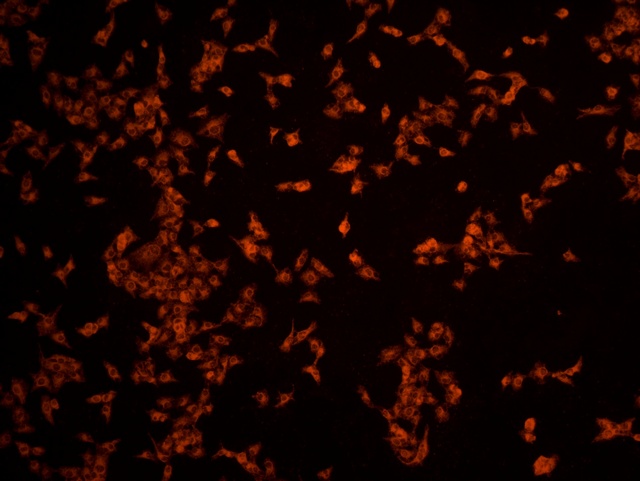

南华大学在生物医学研究领域一直走在学术前沿,近日,该校引进Mshot明美的倒置荧光显微镜MF52-N,搭配显微镜相机MSX2,为细胞切片标本的研究提供了强大的技术支持,进一步提升了科研实力。

MF52-N倒置荧光显微镜以其数显LED荧光模块和深度优化的光路设计,成为细胞切片观察的理想选择。其简单易用的荧光激发操作,大大降低了实验难度,提升了工作效率。同时,该显微镜还能提供高质量的相衬、荧光和明场成像,确保科研人员能够捕捉到细胞切片的每一个细节。

在南华大学的实验室中,科研人员正借助这套先进的显微系统,对细胞切片标本进行深入探索。

此外,MSX2显微镜相机的加入,更是如虎添翼。这款相机以其高分辨率和敏锐的图像捕捉能力,记录了实验过程中的每一个重要瞬间,为数据分析与论文发表提供了有力支持。